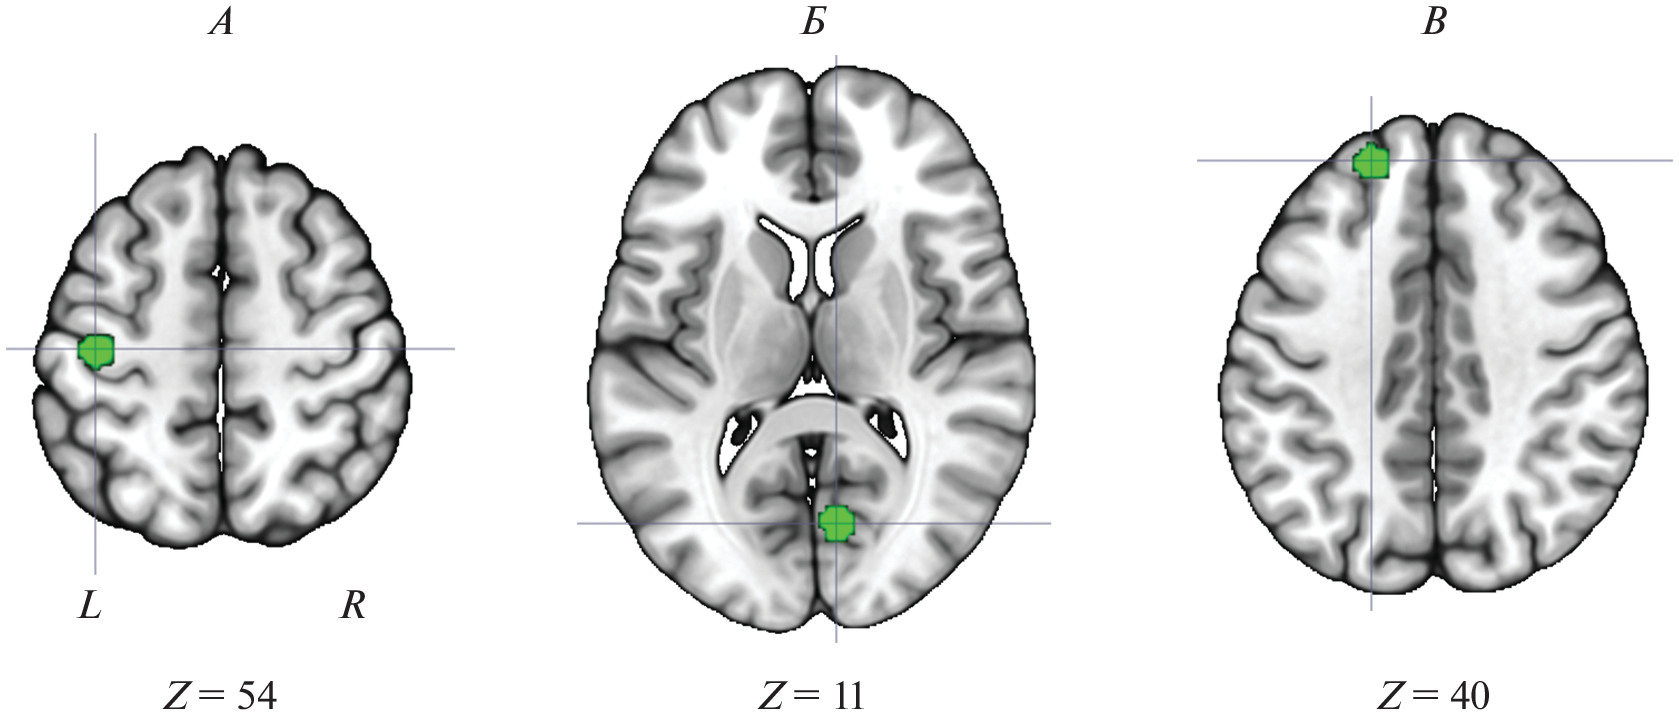

Currently, it is generally accepted that brain functioning is based on the systemic principle. At the same time, knowledge about the principles and mechanisms of the brain system functioning remains scarce. In the present work, these principles were studied within the framework of ideas about the so-called “hidden” nodes of the brain systems. Previously, according to fMRI data, it was shown that some brain structures could be involved in work without changing their energy consumption (reflected by the blood oxygenation level-dependent signal). Their involvement was found only due to a change in the long-range functional connectivity. An analysis of the systemic brain activity using functional connectivity data makes it possible to reveal “hidden” nodes that are inaccessible to detection using the standard “activation” approach. This work aimed to clarify the extent and nature of the involvement of “hidden” nodes in the brain maintenance of various task activities using open fMRI data from the Human Connectome Project. It has been shown that the brain systems ensuring the current activity are provided with a much larger number of nodes than was previously believed, and the overwhelming majority of them are “hidden”. For the first time, this result clearly shows the actual scale of the brain systems providing current activity. The mental activity is actually provided by the work of almost the entire brain and not a minor part of it, as is usually observed in functional tomographic studies. As a result, it is shown that the idea of the existence of “hidden” nodes is confirmed by analyzing the activity of the human brain at the macro-level and shows similarities with the characteristics of the micro-level activity of individual neuronal populations, confirming the previously formulated neurophysiological ideas about the systemic organization of brain activity.

- Киреев М.В., Машарипов Р.С., Коротков А.Д., Медведев С.В. Роль скрытых звеньев в работе мозговых систем обеспечения идентификации и категоризации зрительных стимулов // Физиология человека. 2021. Т. 47. № 6. С. 5. Kireev M.V., Masharipov R.S., Korotkov A.D., Medvedev S.V. Functional Role of Hidden Nodes of Brain Systems Responsible for Visual Identification and Categorization // Human Physiology. 2021. V. 47. № 6. P. 595.